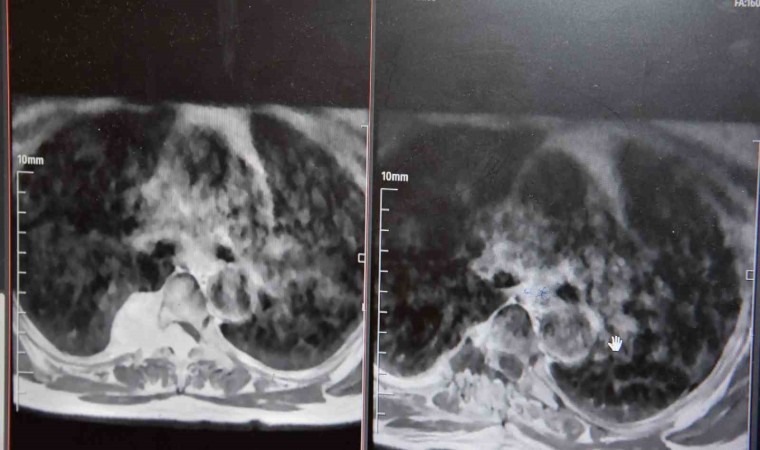

Yol yürümede zorluk bacaklarda uyuşukluk, his kaybı ve güç kaybı şikayetleri ile Çanakkale Mehmet Akif Ersoy Devlet Hastanesinde Beyin Cerrahi Polikliniğine başvuran kadın hasta yapılan tetkikleri sonucunda omurilikte kitle olduğu tespit edildi. Cerrahi operasyon hazırlıkları tamamlanan hasta ameliyata alındı. Kitle yeri nedeniyle oldukça riskli bir pozisyonda olan ameliyat Beyin Cerrahisi Uzmanları ve Göğüs Cerrahisi uzmanlarının da organize bir şekilde katılmasıyla gerçekleştirildi. Ameliyat sonrası servise alınan hasta, tüm şikayetlerinden kurtulması ve sağlıklı bir şekilde yürüyebilmesi üzerine şifa ile taburcu edildi.